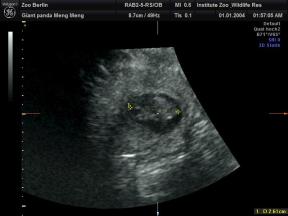

超声波检测到两个胎儿的心跳。

工作人员在园方11日上午进行的超声检查中,清楚地发现了两个熊猫胎儿的心跳。现在两个胎儿的长度约为2.5厘米。